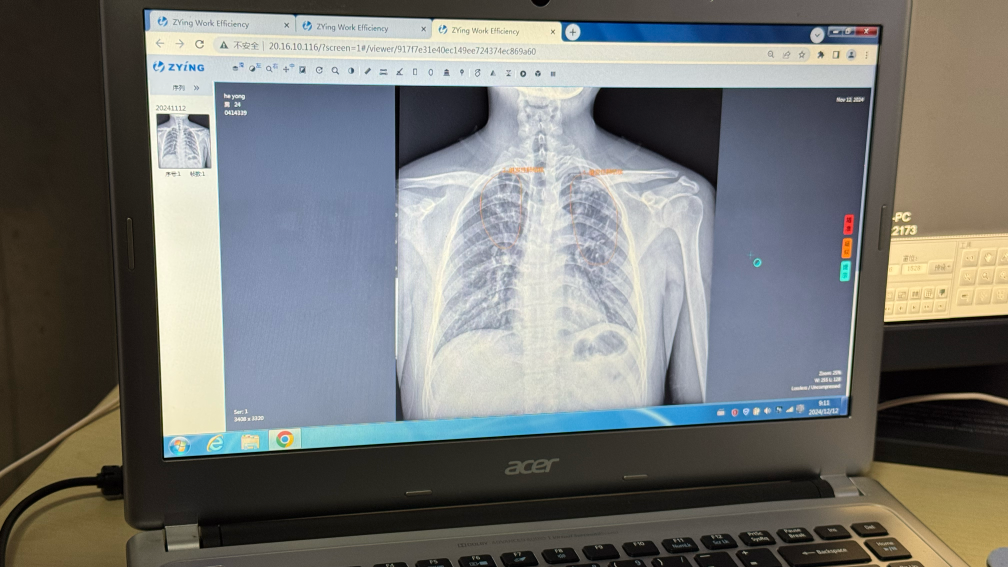

記者在江蘇省走訪時看到,通過將人工智能閱片模型裝入影像科云平臺,全省所有公立醫院和部分民營醫院的醫療機構實現互聯互通,能夠快速篩查患者胸片可疑病灶,并生成自動化報告。

“AI賦能有效提高篩查效率和診斷精確度,尤其是在基層醫療機構發揮了重要作用?!苯K省疾控中心慢性傳染病預防控制所所長竺麗梅說。

江蘇省昆山市第一人民醫院錦溪分院放射科AI云平臺閱片系統。新華社記者顧天成 攝

從AI篩查到全程數據管理,再到全自動一體化微型核酸檢測系統,科技不僅優化了傳統篩查流程,也為“無結核社區”建設、實現“首診即確診”提供了創新解決方案。

江蘇省昆山市第一人民醫院錦溪分院放射科主任湯青燕表示,AI技術不僅能為肺結核篩查提供支持,還促進了包括肺炎、肺癌在內的多種肺部疾病早期發現和診斷。